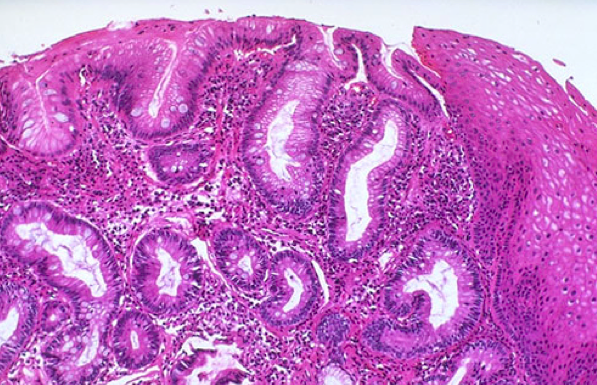

What is going on here?

What do you see here?

What is going on in this esophageal biopsy?